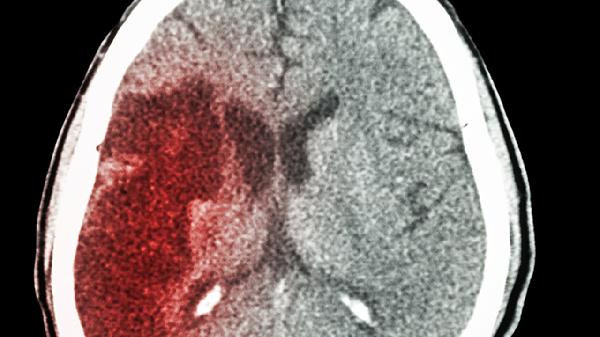

外伤性脑出血可能遗留不同程度后遗症,常见后遗症包括运动功能障碍、认知障碍、语言障碍、情绪障碍及癫痫发作。后遗症严重程度与出血部位、出血量、救治时机及个体康复能力密切相关。

运动功能障碍是外伤性脑出血最常见的后遗症,主要表现为偏瘫、肌张力异常或平衡失调。这与出血灶压迫或破坏运动传导通路有关,如基底节区出血易导致对侧肢体瘫痪。康复治疗需早期介入,包括针灸、运动疗法及器械辅助训练,严重者需长期使用助行器具。